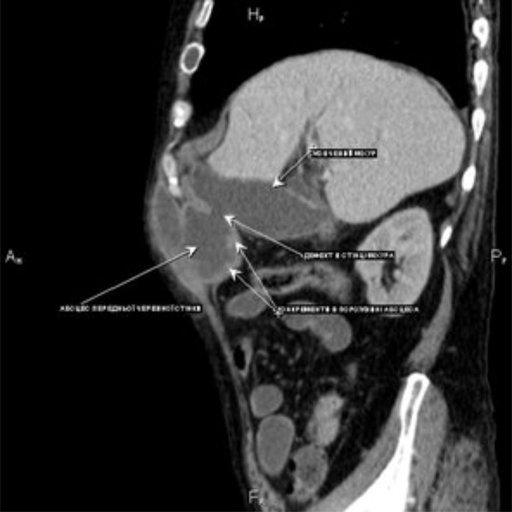

При госпіталізації, зважаючи на суперечливі дані ультразвукової діагностики, 20.01.2017 р. проведено комп’ютерну томографію

Встановлено діагноз гострого деструктивного холециститу з пенетрацією дна жовчного міхура в передню черевну стінку, утворенням фістули та розвитком субапоневротичного міжм’язового абсцесу з анаеробним компонентом. Окрім того, у хворого виявлено холедохолітіаз і механічну жовтяницю (білірубін - 98 ммоль/л).